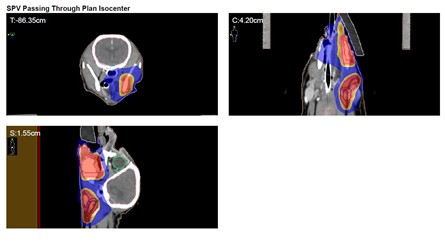

1. 방사선 치료를 위한 모의 CT 촬영

방사선 치료를 위해서는 체계적인 계획이 필요합니다. 이를 위해 먼저 모의 CT 촬영을 진행하여 종양의 크기, 위치를 정확히 파악하고 다른 장기로의 전이가 없는지 확인하였습니다.

✔️ 폐 혹은 림프절로의 전이는 보이지 않았음

2. 방사선 치료 방법 결정

종양의 완전한 국소 제어를 위해서는 20회에 가까운 근치적 치료법도 고려되었으나, 본 강아지 환자의 경우 완치를 목표로 하는 치료보다 노령견의 마취 부담을 줄이고 삶의 질 유지에 초점을 맞춘 완화적 분할 방사선 치료(PRT)를 적용하기로 하였습니다.

✔️ 분할 방사선치료 결정(PRT)

✔️4주에 걸쳐 총 4회의 고선량 방사선 조사